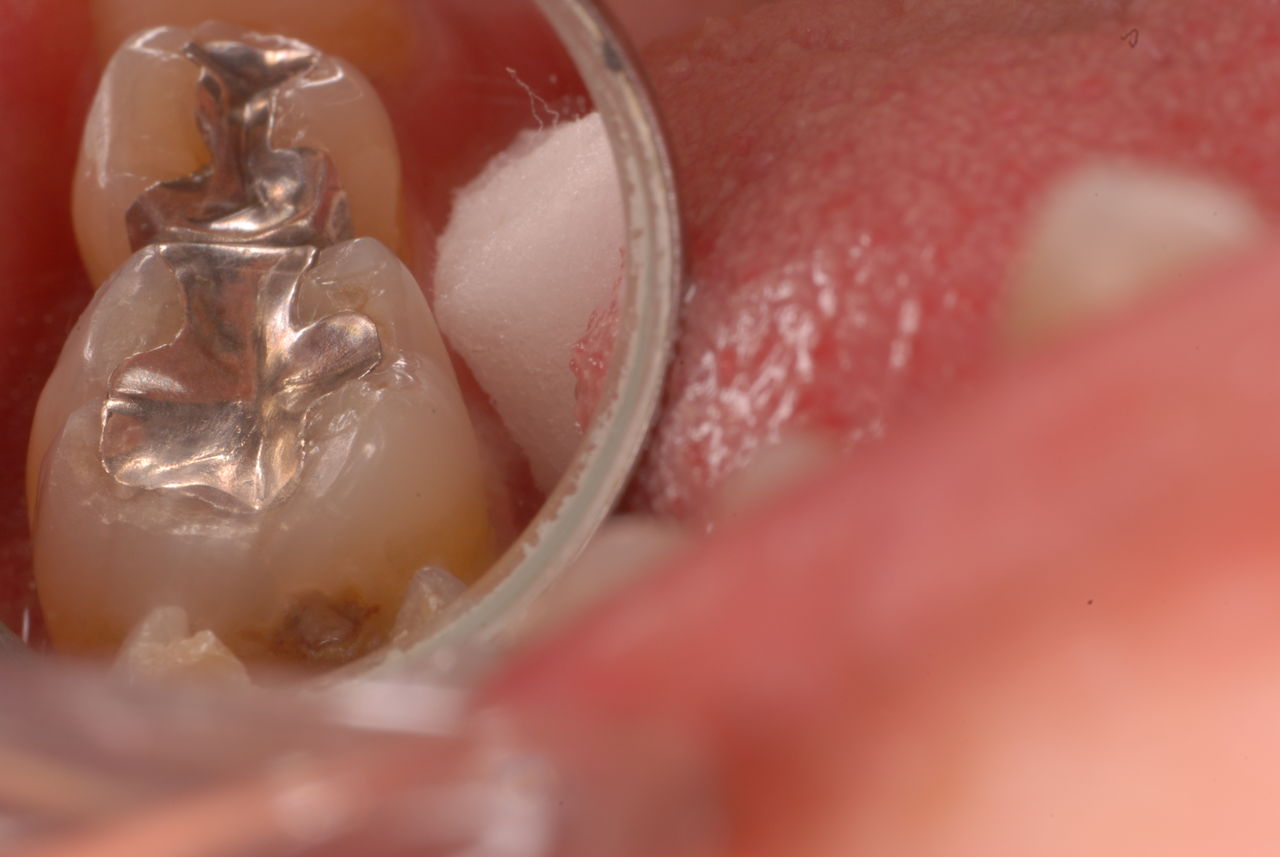

神経が死んでしまった歯は脆いのです。

重症の歯周病で削って上の歯とぶつからないようにしていた歯ですが

いつの間にか神経が死に歯の中が腐っていたようです。

それでヒビが入り割れてしまいました。